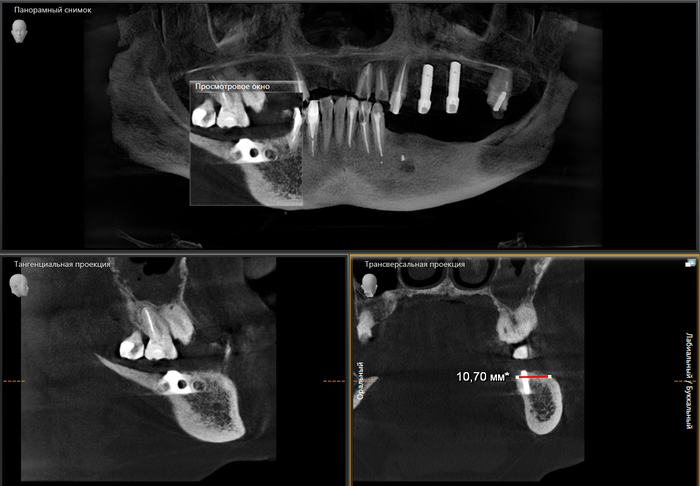

Пациентка достаточно трепетно относится к зубам. Как мы видим, она активно занималась лечением и восстановлением зубов. Но время идет, а следовательно, срок службы пломб, коронок и мостов подошел к концу. Кроме того, что портятся свои зубы, проблемы могут начаться и с установленными имплантатами, как в данном случае. Вторые также приходится удалять. Не говоря уже о том, что некоторые доктора до сих пор устанавливают пластиночные имплантаты без каких-либо показаний. Которые очень легко могут сломаться, как в данном случае. А все почему? Да потому, что не было комплексного подхода, плана лечения и видения ситуации. Вот скажите, зачем сюда «впихнули» тонкую пластину при такой ширине кости? А ведь наверняка перед операцией условия были еще лучше. Ну уж не хуже то точно.

Как мы знаем, у пластиночных имплантатов отсутствует интеграция. Это значит, они не срастаются/не приживаются в кости. Держатся лишь механически. При формировании ложа под имплантат делается «траншея» вдоль альвеолярного гребня, куда в свою очередь помещается данная пластина. Со временем в отверстия этого имплантата прорастает костная ткань. И получается что-то типа замка. Поэтому иным способом кроме как тем, что я указал выше удалить его не удастся. Вы скажете, а разве привычный, цилиндрический имплантат приходится удалять не таким же образом? Акей, теперь сравните площадь раны при удалении пластины около 2 см. в длину, и цилиндра, в среднем 4,5мм в диаметре. Есть разница? Более того, если по каким-то причинам, возникают проблемы с цилиндрическим имплантатом, то как правило, он либо не интегрировался (не сросся с костью), а следовательно, достать его можно и пальцами рук, либо произошла критичная убыль костной ткани вокруг имплантата, как в данном случае. Зачастую работа бормашины или ультразвукового наконечника сводится к минимуму, также, как и травма после манипуляции. Хотя, конечно, это никак не умаляет сложностей, которые связаны с восстановлением объема утраченной кости в этой области. Так как обычно остается внушительная «дыра».

На панорамном снимке ниже по середине четко видны контрастные «белые цилиндры», это как раз и есть тот самый материал, которым были закрыты отверстия в верхнем съемном протезе. Сам протез не рентгеноконтрастен, поэтому его на снимке не видно.

Ну и на десерт. Узрите! Вот оно, ТВАРЬение! Об этом я и говорил, пластиночный имплантат с отверстиями в нем, в которые проросла костная ткань. Ну и сломанный «штырь», который был одной из опор для мостовидного протеза.